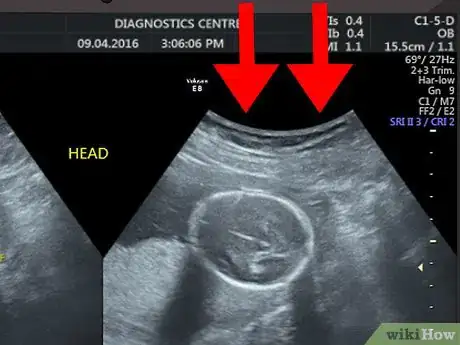

1Disregard the text and numbers at the top of your scan. Most hospitals and ultrasound centers use this space to include details like your name, hospital reference number, or ultrasound machine settings. Since this information does not have anything to do with what you see on the ultrasound image, you can ignore this information.[1]

2Spot the baby. Your baby will also look grey or whitish and will be located within the amniotic fluid (the dark area inside of the womb). Look at the area within your amniotic fluid to try to make out the outline and features of your baby.

- The details that you see in the image will depend on the stage of your pregnancy. For example, at eight weeks, the fetus will look something like a gummy bear or a baked bean; at 12 weeks, you may only be able to identify the head of your baby; while at 20 weeks, you may be able to see the spine, eyes, feet, and heart.[8]